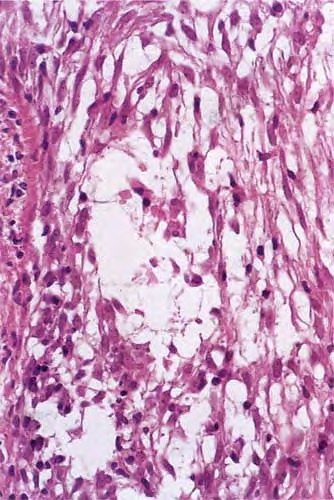

In 1957, Pinkus described alopecia mucinosa, the term used when follicular mucinosis affects terminal hairbearing areas and is associated with hair loss . Papules and plaques may be present or inconspicuous in this form, which may show only alopecia. Scarring is seen more commonly when alopecia mucinosa is associated with cutaneous T-cell lymphoma. Others claim that alopecia mucinosa is simply one of the many morphologic variants of mycosis fungoides , whereas LeBoit and LeBoit acknowledged the paradoxes of alopecia mucinosa that have led to the debate over classification (. Histopathology. Within the outer root sheath and sebaceous gland epithelium, there is reticular epithelial degeneration that sometimes evolves into more extensive cavitation within which mucin is deposited . Occasionally, little mucin can be detected, perhaps because of removal of this water-soluble material in the processing procedure. The deposited mucin is an acid mucopolysaccharide that stains metachromatically with toluidine blue at pH 3.0, as well as with Alcian blue at acid pH. The fact that it can be substantially removed by digestion with hyaluronidase demonstrates that the mucin is predominantly hyaluronic acid. Colloidal iron stain may also be used for its detection. |

Inflammation is composed of lymphocytes and histiocytes, but there can also be eosinophils. There may be exocytosis into the outer root sheath epithelium of the infundibulum and the sebaceous gland epithelium. Although individual pathologic criteria are not absolutely diagnostic of the type of |

follicular mucinosis (primary or secondary), features that have been proposed as favoring a lymphoma-associated lesion include an atypical lymphocytic infiltrate or increased density of the perifollicular infiltrate with substantial folliculotropism . This study also suggested that a prominent eosinophilic infiltrate and more substantial mucin deposition tend to favor a benign process, but a subsequent study failed to substantiate these findings . |

Pathogenesis. Electron microscopic studies have shown that the mucin is a product of the outer root sheath epithelial cells. The cytoplasm shows prominent, dilated, rough-surfaced endoplasmic reticulum containing fine, granular, filamentous material that is secreted into the intercellular spaces . In two of our patients with primary, idiopathic alopecia mucinosa with reversible alopecia, we found, using transverse sections, an increased |